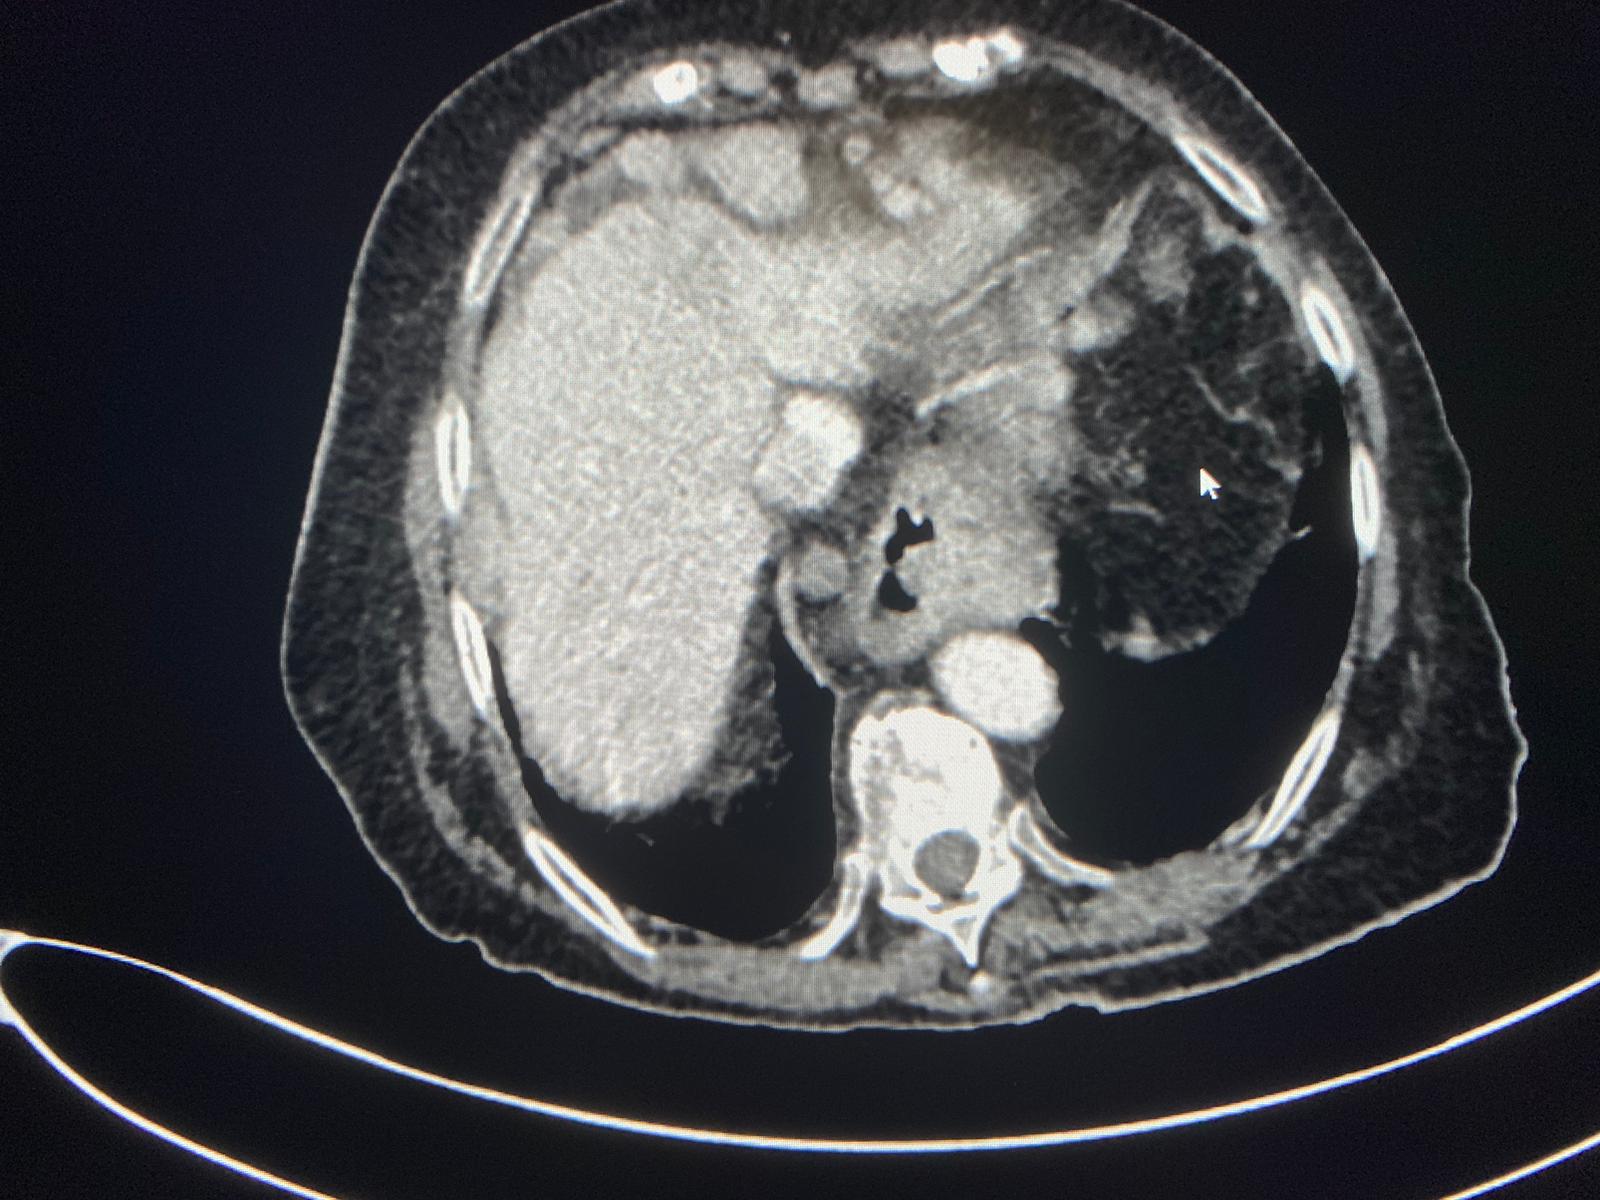

| Llaman por sospecha de colecisitis en mujer de 95 años. Se hace el TC y vemos una gran masa heterogènea hepática, que condiciona dilatación de via biliar intra y extra, junto con múltiples implantes perihepàticos, periportales, periesofágicos, intrapelvicos… Se sospecha de colangiocarcinoma, menos probable hepatocarcinoma. |